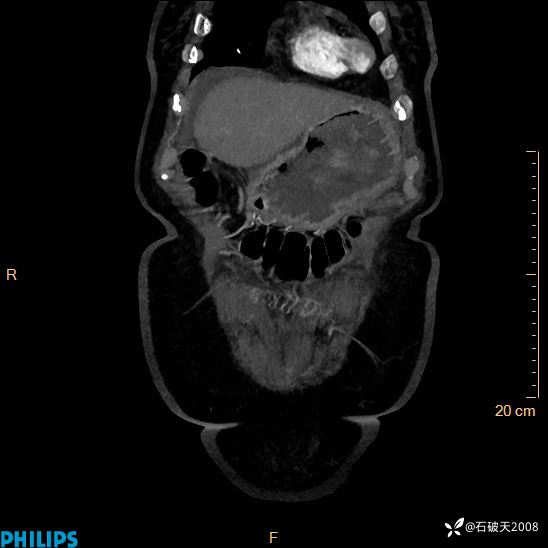

女82岁 主 诉:腹痛半月,加重3天

现病史:半月前患者无明显诱因出现腹痛,上腹部、下腹部间断隐痛,进食后明显,腹胀,大便干,无反酸、烧心,无恶心、呕吐,无腹泻、发热,无咳嗽、咳痰,无心慌、胸闷、无头痛、头晕,无粘液脓血便等症状,患者就诊XXXX医院,给予中草药治疗(具体药物不详)治疗,效差,3天前患者腹痛较前加重,上腹部、下腹部间断隐痛,伴间断性绞痛,今为求进一步诊治来诊我院,门诊以“腹痛”为诊断收住院,自发病来神志清,精神差,饮食差,睡眠一般,小便正常,体重无明显变化。

MIP